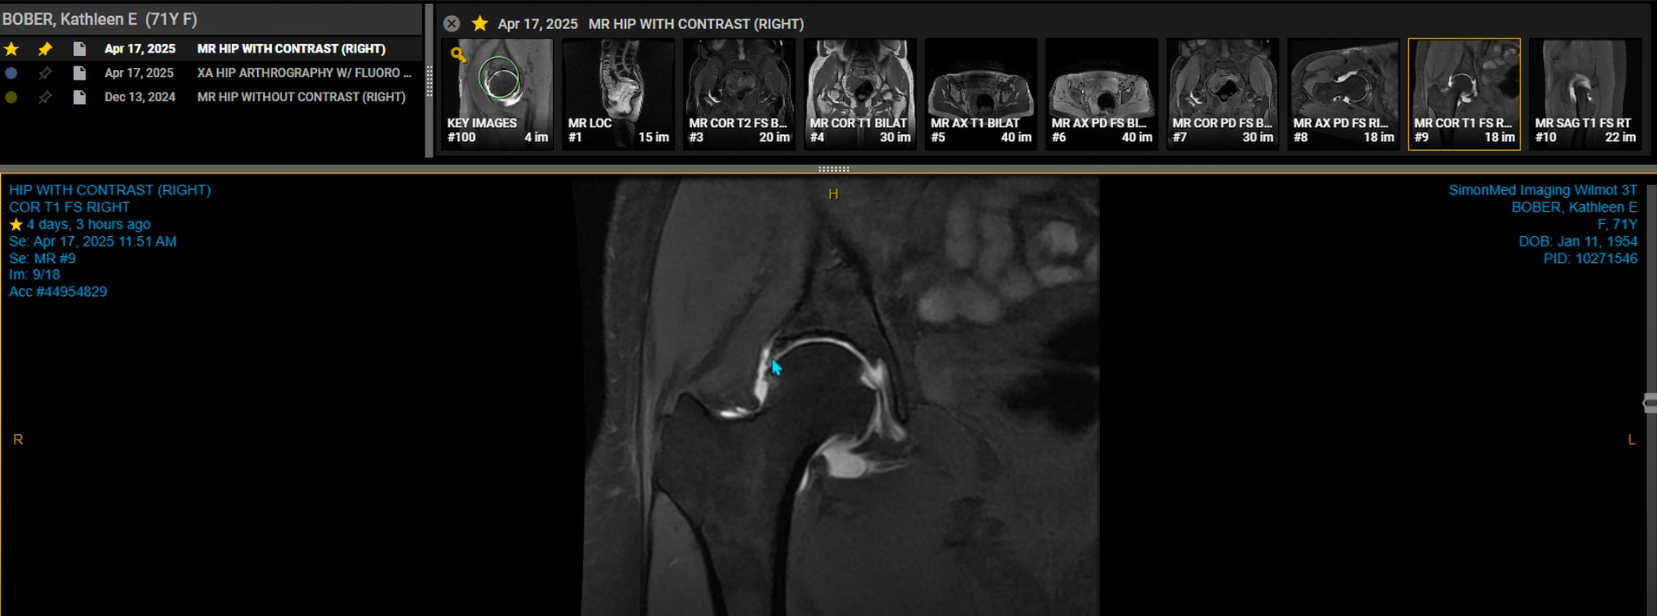

A hip MRI with contrast, also known as MRI arthrography, is a specialized imaging technique used to visualize the structures within the hip joint in greater detail. It involves injecting a contrast agent, usually gadolinium, directly into the hip joint before taking MRI scans. This helps to highlight the labrum, cartilage, ligaments, and other soft tissues, making it easier to identify injuries or abnormalities. My MRI results showed no evidence of osteonecrosis, moderate to severe OA, and labral degeneration without flap tear (the blue arrow in the 2nd image points to the area of labral degeneration).